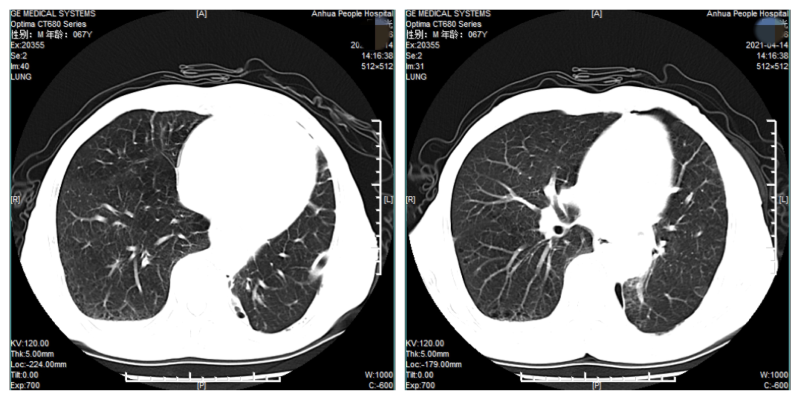

手术过程顺利,历时3小时余,出血量约20ml,术后顺利拔除气管插管,安返普通病房。予以常规输氧、心电监护,积极抗感染、化痰、补液等处理,术后6小时即嘱患者饮水、进食。术后24小时拔除导尿管,撤除心电监护,协助下床活动。术后5天复查CT,提示余肺复张良好,无明显胸腔积液。切口如期拆线,顺利出院。

术后影像